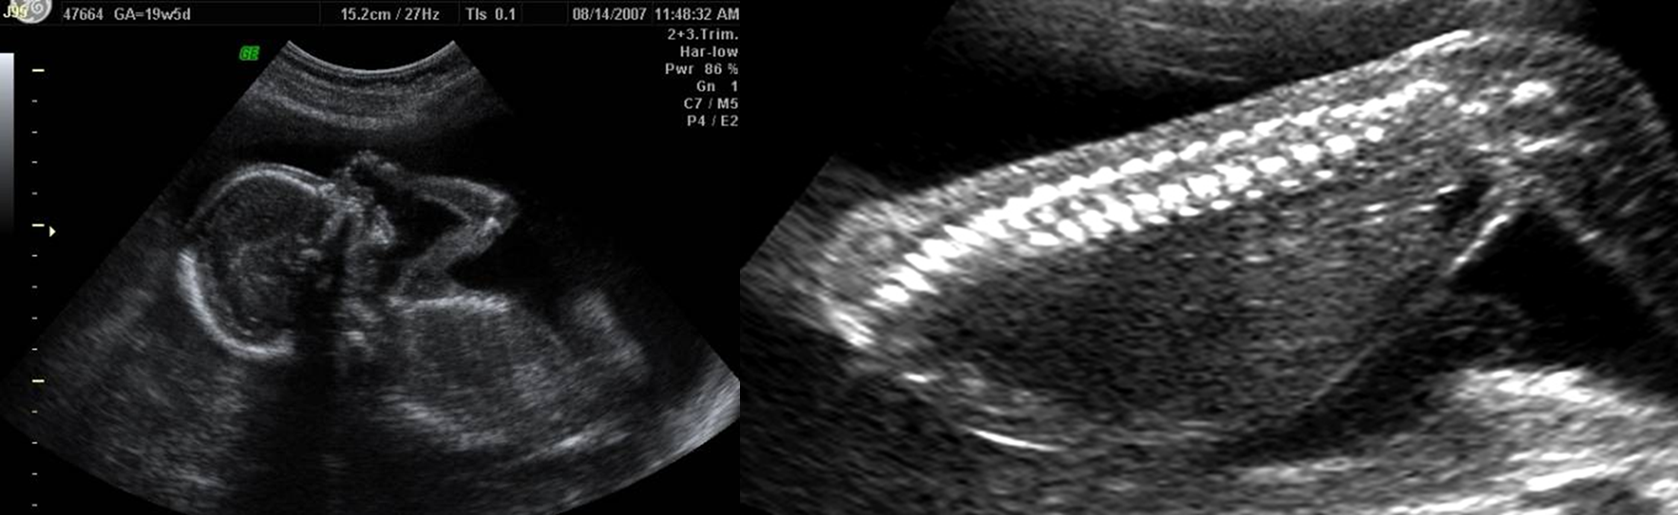

It is assessed by performing biophysical profile. We measure the following.

1. Amniotic fluid volume

2. Movement of body

3. Flexion and extension of limb

4. Respiratory rate